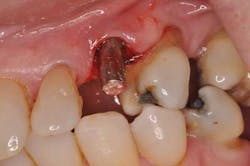

A new patient presents to my office with a chief complaint: “My implant crown fell off yesterday.” She’s a 72-year-old woman with noncontributory medical history. She states the implant in tooth position No. 11 was placed “a few years ago and never felt right.” Examination reveals a prefabricated abutment of some sort that is not mobile. Curiously, the peri-implant gingiva has a slight erythema. Moderate bleeding is noted upon insertion of the implant crown.

Fig. 1: Implant crown seated.

Fig. 2: Moderate bleeding noted around prefabricated abutment after crown is removed.